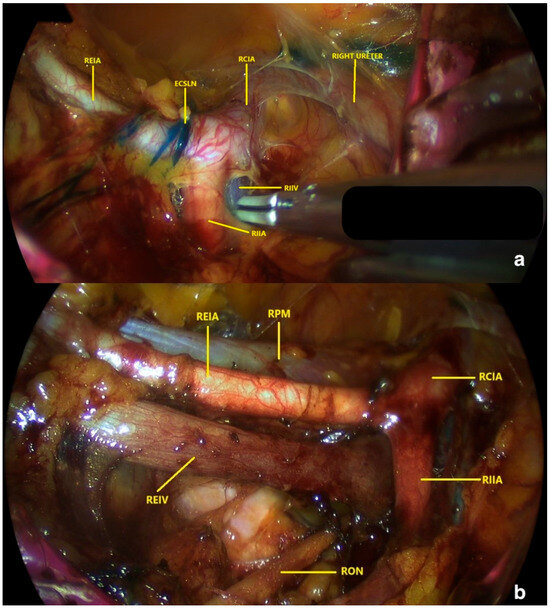

Does Retroperitoneal vNOTES Sentinel Lymph Node Mapping Represent a Feasible Staging Option in Presumed Early-Stage Endometrial Cancer?

Background and Objectives: Sentinel lymph node (SLN) mapping is an established alternative to systematic lymphadenectomy for early-stage endometrial cancer (EC). While retroperitoneal vNOTES affords direct access to pelvic nodes without abdominal incisions, data regarding its oncologic validity remain sparse. This study evaluates [...] Read more.

Background and Objectives: Sentinel lymph node (SLN) mapping is an established alternative to systematic lymphadenectomy for early-stage endometrial cancer (EC). While retroperitoneal vNOTES affords direct access to pelvic nodes without abdominal incisions, data regarding its oncologic validity remain sparse. This study evaluates the SLN detection rates, perioperative outcomes, and 12-month oncologic outcomes oncologic results of retroperitoneal vNOTES mapping in presumed early-stage EC. Materials and Methods: This single-center retrospective cohort study analyzed consecutive patients undergoing retroperitoneal vNOTES staging (hysterectomy, BSO, and SLN mapping) for presumed EC between February 2023 and January 2024. Eligible patients had radiologically uterine-confined disease and were candidates for transvaginal surgery. Following cervical methylene blue injection, SLN mapping was executed via the retroperitoneal vNOTES route. Mapped and suspicious nodes were excised, with side-specific lymphadenectomy performed for failed mapping per algorithm. While perioperative outcomes were assessed for the full cohort, oncologic analyses (FIGO 2023 staging, nodal metastasis) were restricted to patients with confirmed carcinoma. Results: Of 98 patients (median age 54; BMI 31 kg/m2), final pathology confirmed carcinoma in 78 (73 endometrioid, 5 serous) and EIN in 20. Bilateral SLN mapping succeeded in 87.8% (86/98), necessitating side-specific lymphadenectomy in the remaining 12.2%. The obturator fossa was the predominant nodal basin (43.9%). Within the carcinoma cohort (n = 78), 57.7% were Grade 1 and 74.4% FIGO Stage I. Nodal metastases (FIGO IIIC1) were identified in 12.8% (10/78), all prompting adjuvant therapy. At a median follow-up of 12 months, no disease recurrences were observed. The complication rate was 6.1% (5.1% Clavien–Dindo ≥ III), with no conversions required. At 12-month follow-up, no recurrences were detected, though the absence of systematic lymphadenectomy precluded formal sensitivity analysis. Conclusions: Retroperitoneal vNOTES represents a feasible and safe strategy for SLN mapping in early-stage EC, demonstrating high bilateral detection with minimal morbidity. However, reliance on methylene blue and limited follow-up necessitate caution. Broader implementation requires validation through prospective, comparative trials utilizing indocyanine green and long-term oncologic surveillance. Full article